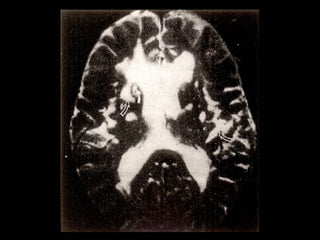

Functional Neuroimaging (PET,SPECT)

demonstrates decreased metabolic activity in

 Dorsal   prefontal cortex

– Anterolateral (concentration, cognitive

processing)

– Cingulate (regulation of mood and affect)

 Subcortical

– Caudate (psychomotor changes)